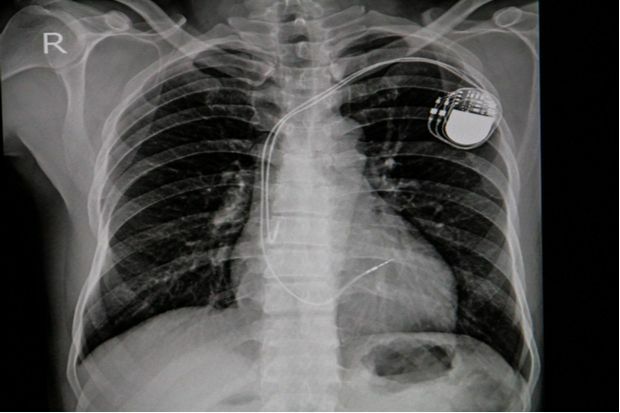

What advice can you give to a patient having a pacemaker fitted?

A patient is having a pacemaker fitted. But what advice can you give them on how it will work and the procedure they will undergo to have it fitted?